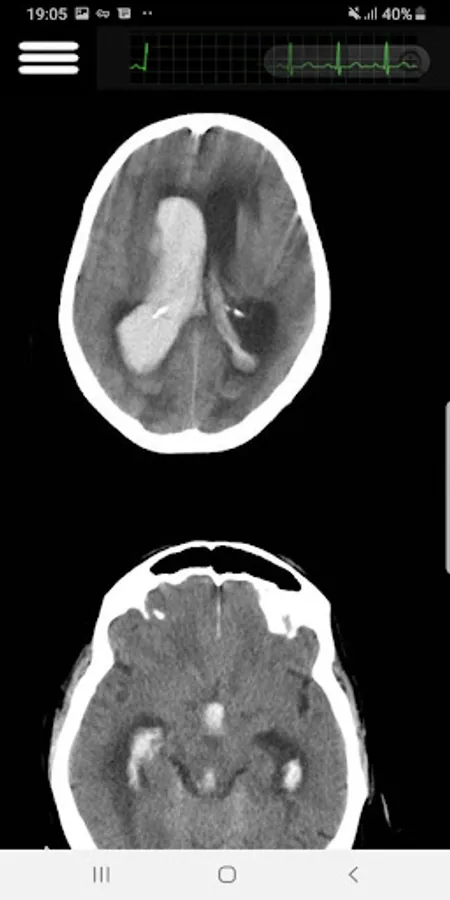

In this app, I covered the most important Head CT-Scan features that a practitioner face in his clinic or in an ER. Subjects like Hoe to read in an organize way, Blood, cisterns, Brain, Ventricles and bone.